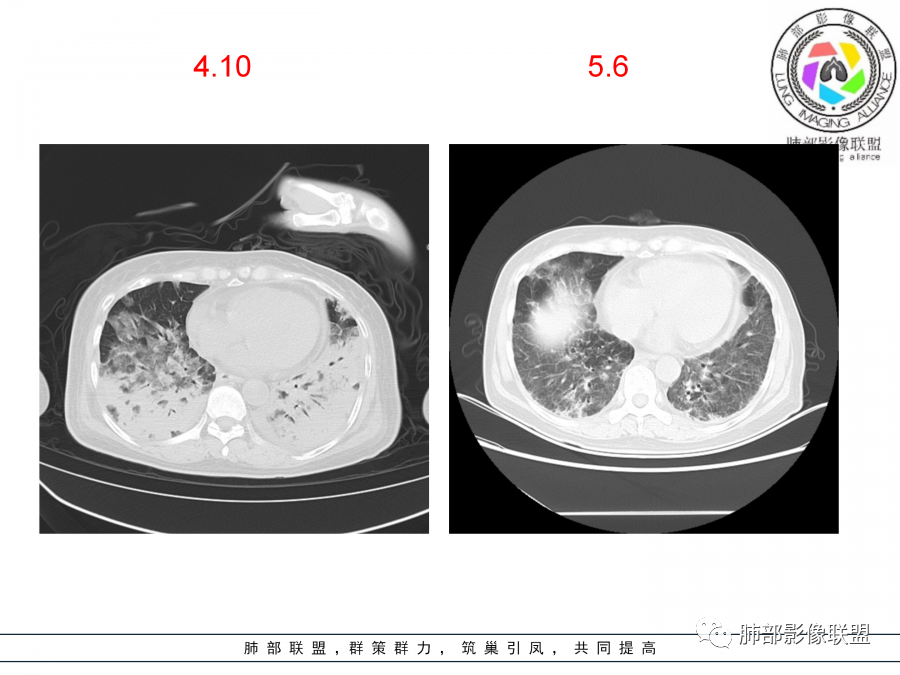

影像,第一次双肺中下叶胸膜下多发斑片状实变影,部分融合成,周围散发磨玻璃影,磨玻璃影内可见小叶间隔及小叶内间隔增厚,病变平行于胸膜,第二次间隔8天,双肺实变影明显进展,有重力作用,支气管近端堵塞,进展较快,临床有发热,血沉高,狼疮SLE阳性,考虑1:OP(机化性肺炎)2:SLE相关肺炎,建议支气管镜灌洗液病原学检测。

第一次双肺中下叶胸膜下多发斑片状磨玻璃及实变影,病变平行于胸膜,支气管通畅,8天后,双肺实变影明显进展范围扩大,部分支气管近端堵塞,进展较快,胸腔积液,抗感染治疗无效,考虑:非感染性疾病:结缔组织相关性肺病。鉴别机化性肺炎。

外围胸膜下,实变+GGO+网格,支气管通畅

提示间质为主病变